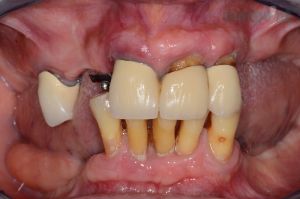

Régi implantátumok cseréje, fémmentes koronák felhelyezése

Fiatal hölgy páciensünk a 10 évvel ezelőtt behelyezett implantátumainak csontpusztulása és ínyének visszahúzódása miatt keresett fel minket. A régi implantátumok eltávolítását követően újakat helyeztünk be, és ínyplasztikai kezeléssel, valamint cirkónium egyéni implantátum fejekre készített e.max fémmentes kerámia koronákkal adtuk vissza páciensünk elégedett mosolyát.

Implantáció, fogpótlások: Dr. Molnár Bálint

1) Kiindulási helyzet